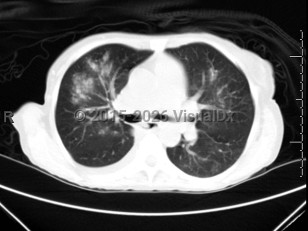

This viral illness may manifest differently depending on patient age, health status, and whether it is a primary or secondary infection. RSV symptoms in most patients are mild and consist of nasal congestion, rhinorrhea, sneezing, decreased oral intake, cough, and sometimes a fever. In younger patients, especially those younger than age 3 months and premature infants, RSV may cause bronchiolitis (inflammation of the small airways in the lungs) or a viral pneumonia that presents with runny nose, irritability, wheezing, increased work of breathing, and hypoxemia. In very young infants, apnea may be one of the first presenting symptoms. RSV may also present as a croup-like illness with a barking cough and stridor. Among infants and young children with primary infection, the disease may present as LRTI with bronchiolitis or pneumonia. In hospitalized infants, 20% have or develop apnea. Apnea is more likely to be seen in premature infants and in those with severe hypoxemia. Older children and adults are more likely to have symptoms of URTI or tracheobronchitis. RSV is also known to be an important factor leading to acute otitis media in young children with bronchiolitis. However, in older adults and immunocompromised individuals, these conditions may progress to a severe LRTI. In a study of adult SOT recipients, the most common symptoms included fever, cough, and dyspnea. Less common symptoms included rhinorrhea and wheezing.